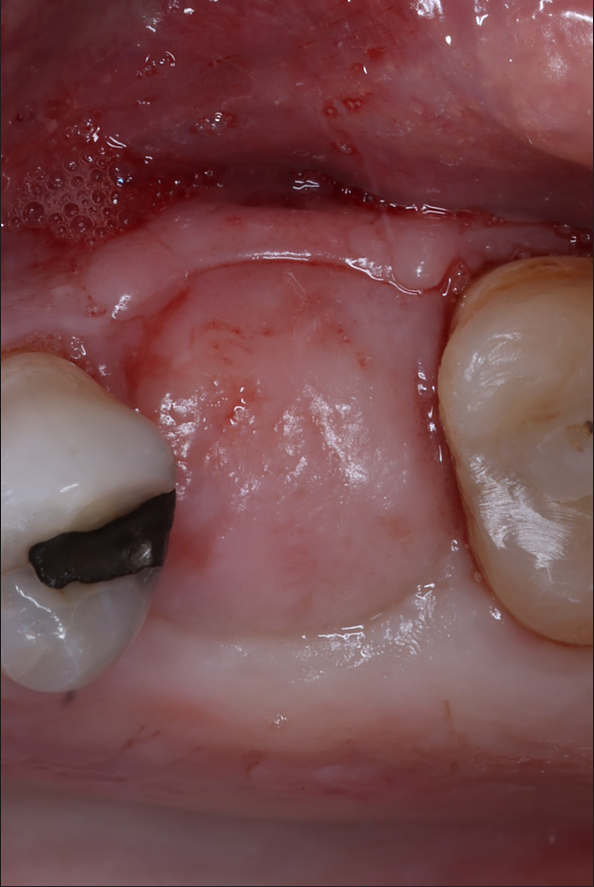

Patient returned at six weeks and the PTFE membrane and sutures were removed and he was healing as expected.

At four months, patient returned and records were made for the implant process. Records showed good bone fill and good bone height, the implant was planned on exocad software and a guide was fabricated.

Couple things about this case, I chose to do a tissue punch because the width of the ridge and the amount of attached tissue present. When we use the PTFE membrane for socket preservation, we ultimately grow nice, thick attached tissue, and this is a perfect example of that. I probably only do one or two tissue punches a year.

Notice in the final pictures, the amount of attached tissue is greater around the implant that it is around the natural teeth. Bone is obviously important for implants, but attached tissue will determine how long they last and how healthy they stay.